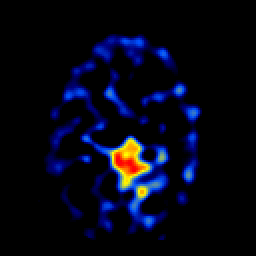

SPECT TL Study #6 -- Slice #41

[Home][Help][Clinical][Tour 1][Tour 2][Tour 3] Slice 41